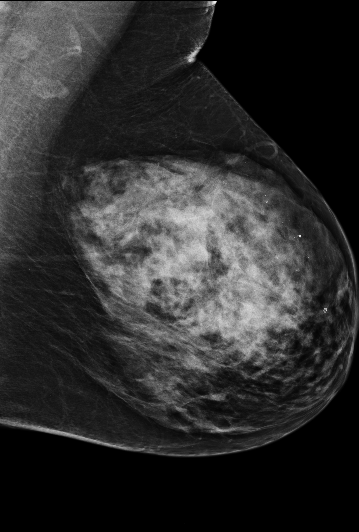

Masking refers to the phenomenon in which a tumor is hidden by the surrounding breast tissue, causing the cancer to be difficult or even impossible to discern with regular mammography, as seen in Figure 2. Masking can also result in large invasive cancers111We define large invasive cancers as those confirmed to have spread and be 2cm at time of diagnosis. – a small cancer may be difficult to discern in certain images, allowing it to grow to a more lethal size. Masking is correlated with breast density, as it has been shown that cancer in dense breasts is more likely to be missed during screening [5, 6, 7]. Density can be subjectively assessed by radiologists via the BI-RADS density standard (ACR) [8, 9], or measured by automated tools such as Libra [10]. These density measurements, however, do not perfectly correlate with masking potential. Radiologists consider the distribution and pattern of tissue when assessing masking potential, and have called for automated methods to assess the masking effect [11]. Until now, the question of exactly how masking potential should be quantified remains an open one, although some subjective notion has been added to certain categories of the most recent edition of BI-RADS density [12].

| Large invasive cancer | Same cancer, likely masked | Tumor size & frequency | |